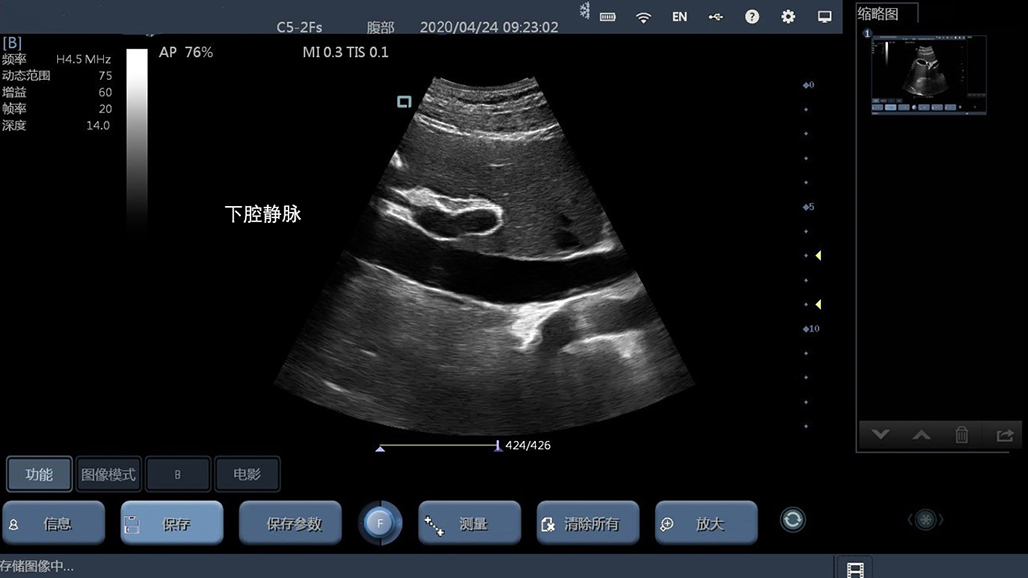

• 大凸

腹部

肾脏

妇科产科

心脏

肺等